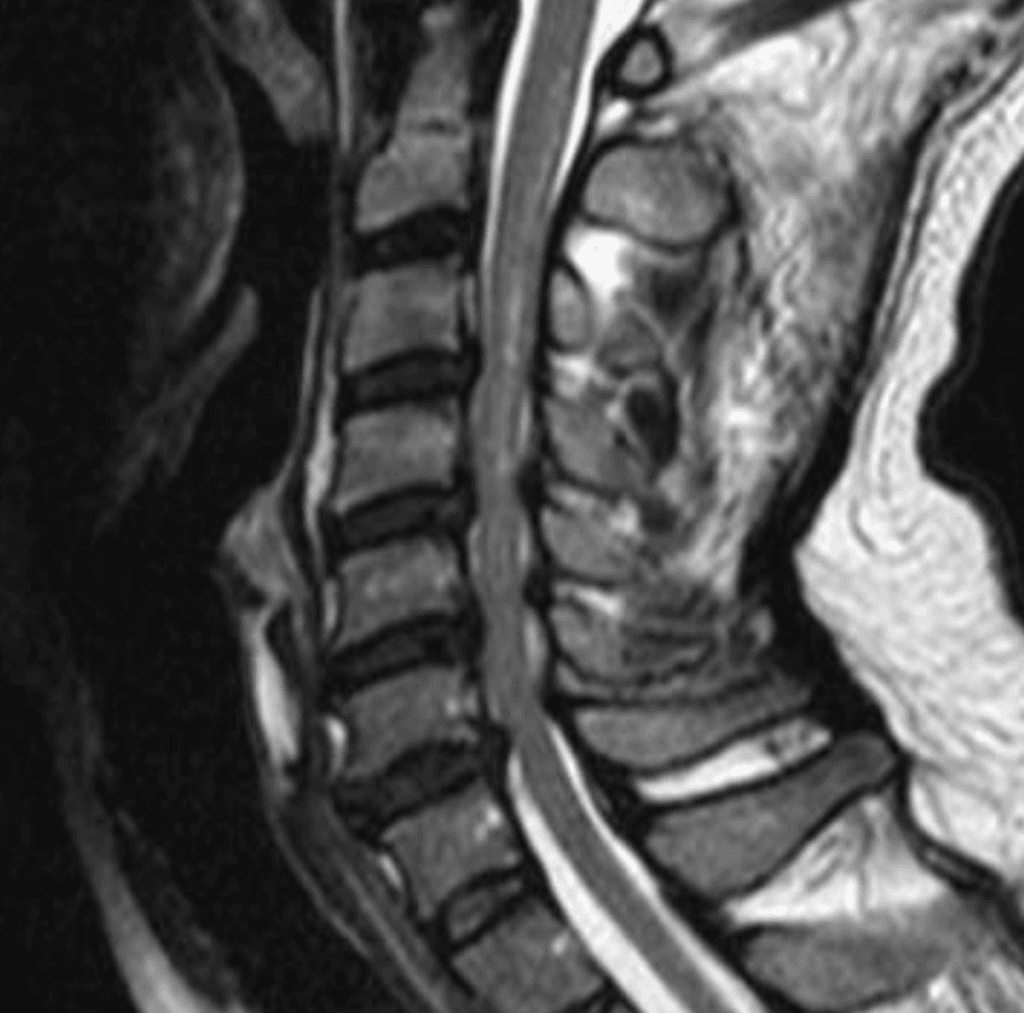

Canal cervical estrecho laminoplastia

Masculino, 46

Cervicobraquialgia bilateral progresiva, contractura muscular crónica.

Alteración en coordinación de movimientos de los dedos de las manos, dificultad para la prensión.Alteración de la marcha. Parestesias y sensación de frío en MMII.

Canal Cervical Estrecho (CCE)

Ver caso real de tratamiento del CCE por laminoplastía. La estenosis del canal cervical constituye una entidad patológica...